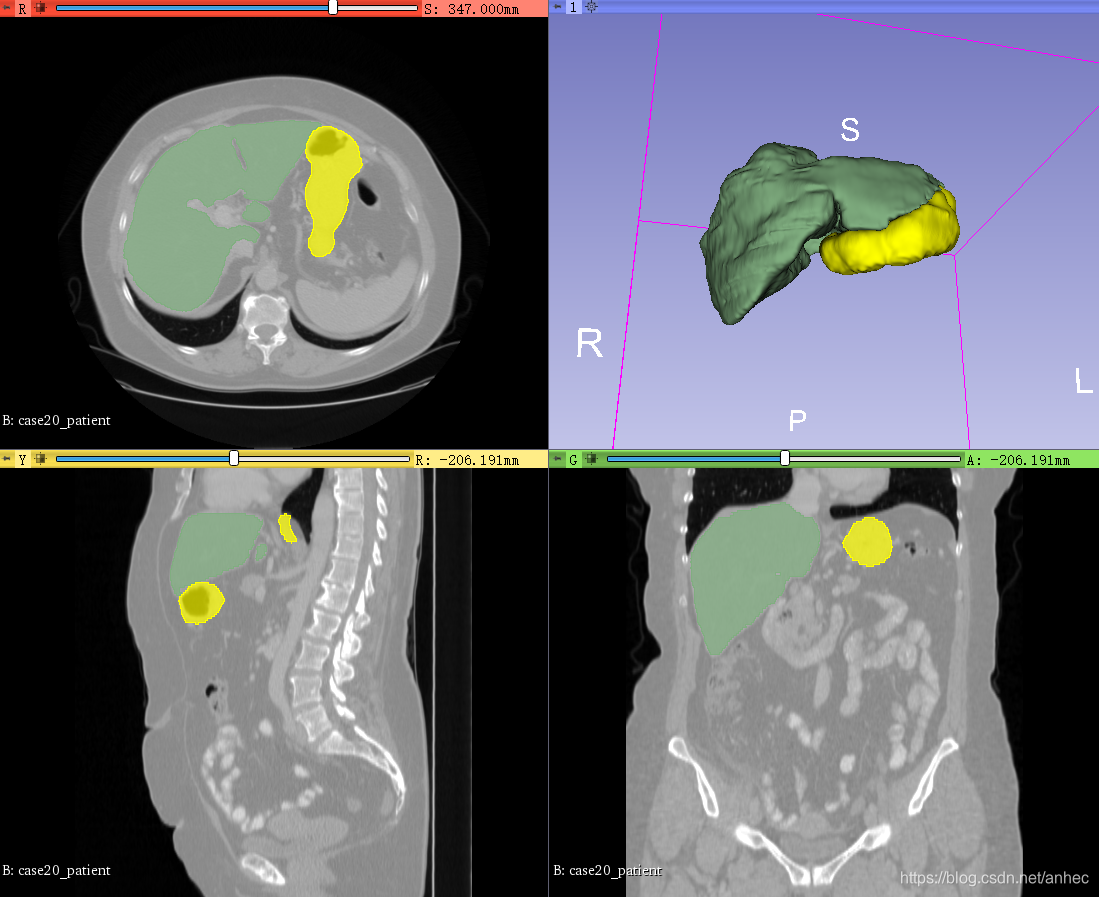

就可以看到label在原始体数据上的叠加效果:

就可以看到label在原始体数据上的叠加效果: